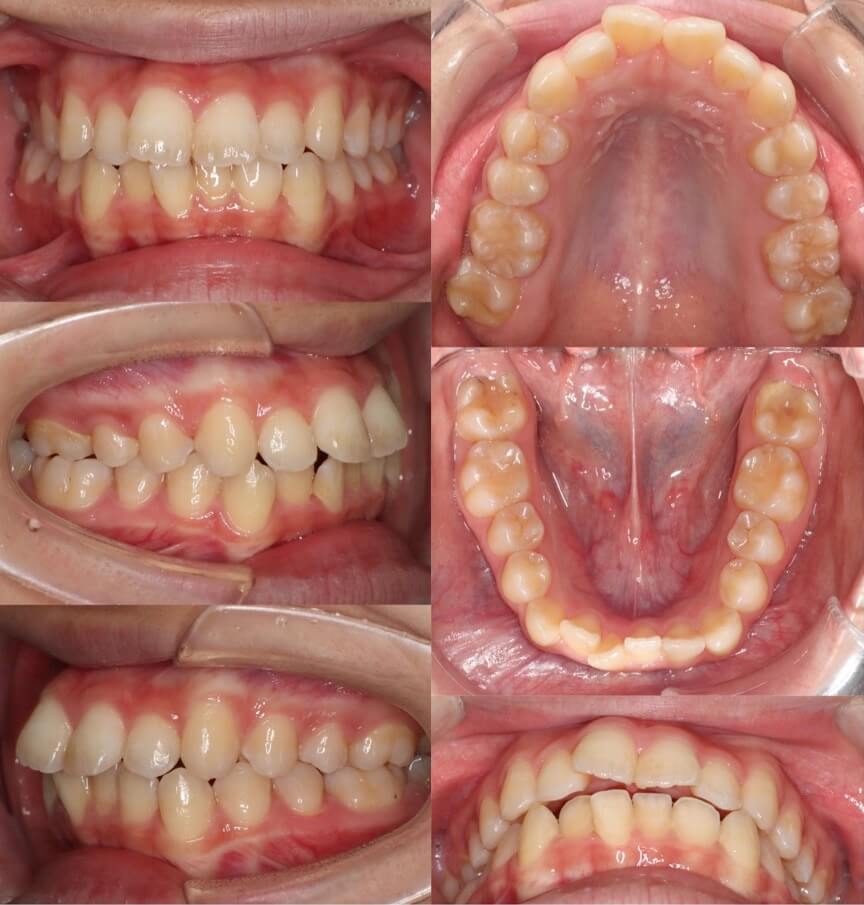

「男性は顔が引き締まる」

高校生男性・唇側矯正装置・下あご後退型

当初は、抜歯矯正治療にするかしないかで、治療方針に迷ったケースですが、最終的には患者さんの希望に沿って抜歯矯正治療にしました。歯の動きがゆっくりであったため、治療期間が3年を超えてしまいました。

<症例概要> 難易度:★★★★☆

主訴:口元の突出・前歯のガタツキ

年齢・性別:高校生男性

住まい:千葉県八千代市市

症状:下顎後退・叢生

治療方針:抜歯空隙の閉鎖(最大固定)

治療装置:唇側矯正装置

固定:歯科矯正用アンカースクリュー(頬側x2)

抜歯:上下第一小臼歯(計4本)

治療期間:3年4か月

リテーナー:上下プレートタイプ+フィックスタイプ

治療費用:968,000(税込)

代表的副作用:痛み・治療後の後戻り・歯根吸収・歯髄壊死・歯肉退縮